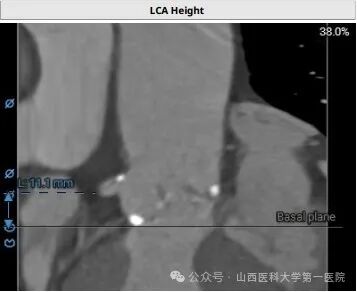

郭建军主任医师介绍,TAVI手术是一种微创心脏瓣膜置换手术,通过股动脉或心尖途径,将人工瓣膜植入以替换病变或异常的主动脉瓣膜。相较于传统开胸手术,TAVI手术对患者身体损伤小、术后恢复快、死亡率也大大降低,然而手术要求精细至毫米级,技术难度极高,必须在多学科专业团队协作下在专门杂交手术室内实施。该患者情况尤为复杂,主动脉及主动脉瓣钙化严重、左右冠脉开口位置低,手术风险极大,在郭建军主任医师团队的精湛技艺和全体参与人员的共同努力下,手术获得圆满成功。